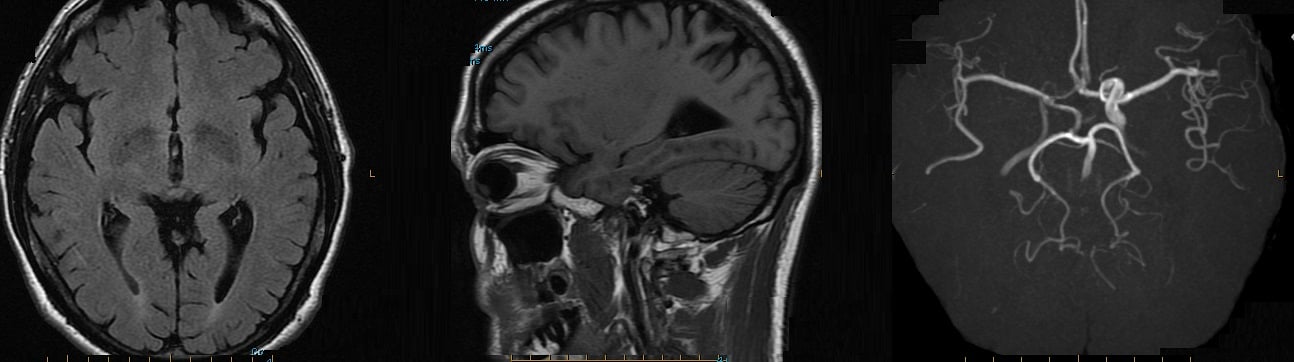

Fish consumption improved brain volume in the frontal lobes, temporal lobes (including the hippocampus) and posterior cingulate gyrus, as shown on high-resolution, three-dimensional volumetric magnetic resonance imaging (MRI). "That's important because these are areas of the brain that are responsible for memory and learning and are severely affected by Alzheimer's disease," reported Dr. Cyrus A. Raji of the University of Pittsburgh. Dr. Raji and his colleagues analyzed data collected at three time points from the ongoing Cardiovascular Health Study-Cognition Study. In 1989-1990, 260 subjects (mean age 71 years) completed standardized diet questionnaires. In 1998-1999, these individuals (mean age 78 years) underwent volumetric MRI. An analysis of clinical conversion to mild cognitive impairment (MCI) or Alzheimer's disease (AD) in 2002 among study participants (mean age 82 years) found that individuals with larger brain volumes as a result of weekly baked or broiled fish consumption had a greatly reduced incidence of MCI or AD, compared with individuals who did not eat fish regularly. Clinical conversion rates to MCI or AD were 30.8% for non–fish eaters, compared with 8% for individuals whose brains benefited partially from fish consumption (as shown on volumetric MRI), and 3.2% for individuals whose brains benefited fully from fish consumption. These findings indicate "a large reduction in the risk for developing AD or MCI as a result of consuming baked or broiled fish," Dr. Raji said The benefits of regular fish intake persisted even after accounting for such potential confounding variables as age, gender, head size, and cerebrovascular disease. Study participants who were not fish eaters and who showed atrophy in the hippocampus – the region most frequently affected by AD – had a 47% incidence of MCI or AD, compared with only 28% of fish eaters with larger hippocampal volumes, he reported. In addition, mean scores on cognitive tests of working memory were significantly higher (P less than .05) in individuals who ate fish weekly compared with those who did not. The improvement remained even after accounting for potential confounders such as age, gender, and education. The researchers also looked at cognitive test scores and brain volumes and found a relationship between larger frontal lobe volumes in fish eaters and higher working memory test scores. "This makes a lot of sense, because the frontal lobes are responsible for working memory function," Dr. Raji said. The reduced risk of MCI and AD among fish eaters in this study probably stems from the protective benefits of omega-3 fatty acids, he noted. Omega-3 fatty acids are believed to increase blood flow to the brain, act as antioxidants and anti-inflammatories, and prevent the accumulation of the amyloid plaques characteristic of AD. Consumption of fried fish, which is high in cholesterol and low in omega-3 fatty acids, did not confer any benefits.Data presented by Dr. Raji at last year's meeting of the Radiological Society of North America (Internal Medicine News, Dec. 20, 2010) showed the protective benefits of physical activity in preserving brain volume and reducing the risk of AD and MCI in the same cohort. "What we're adding to the picture this year is specific information on diet," he said. "The long-term goal of this research is to incorporate our understanding of all the various lifestyle factors that could reduce risk and give us a unified picture of how to best prevent the disease." Dr. Raji had no disclosures related to this study.

Regular fish intake lowers dementia risk

December 2, 2011, BY SUSAN BIRK CHICAGO (EGMN) – Consumption of baked or broiled fish on a weekly basis improved brain health and significantly reduced the risk of mild cognitive impairment and Alzheimer's disease in a 20-year longitudinal study of older adults presented at the annual meeting of the Radiological Society of North America.Fish consumption improved brain volume in the frontal lobes, temporal lobes (including the hippocampus) and posterior cingulate gyrus, as shown on high-resolution, three-dimensional volumetric magnetic resonance imaging (MRI). "That's important because these are areas of the brain that are responsible for memory and learning and are severely affected by Alzheimer's disease," reported Dr. Cyrus A. Raji of the University of Pittsburgh. Dr. Raji and his colleagues analyzed data collected at three time points from the ongoing Cardiovascular Health Study-Cognition Study. In 1989-1990, 260 subjects (mean age 71 years) completed standardized diet questionnaires. In 1998-1999, these individuals (mean age 78 years) underwent volumetric MRI. An analysis of clinical conversion to mild cognitive impairment (MCI) or Alzheimer's disease (AD) in 2002 among study participants (mean age 82 years) found that individuals with larger brain volumes as a result of weekly baked or broiled fish consumption had a greatly reduced incidence of MCI or AD, compared with individuals who did not eat fish regularly. Clinical conversion rates to MCI or AD were 30.8% for non–fish eaters, compared with 8% for individuals whose brains benefited partially from fish consumption (as shown on volumetric MRI), and 3.2% for individuals whose brains benefited fully from fish consumption. These findings indicate "a large reduction in the risk for developing AD or MCI as a result of consuming baked or broiled fish," Dr. Raji said The benefits of regular fish intake persisted even after accounting for such potential confounding variables as age, gender, head size, and cerebrovascular disease. Study participants who were not fish eaters and who showed atrophy in the hippocampus – the region most frequently affected by AD – had a 47% incidence of MCI or AD, compared with only 28% of fish eaters with larger hippocampal volumes, he reported. In addition, mean scores on cognitive tests of working memory were significantly higher (P less than .05) in individuals who ate fish weekly compared with those who did not. The improvement remained even after accounting for potential confounders such as age, gender, and education. The researchers also looked at cognitive test scores and brain volumes and found a relationship between larger frontal lobe volumes in fish eaters and higher working memory test scores. "This makes a lot of sense, because the frontal lobes are responsible for working memory function," Dr. Raji said. The reduced risk of MCI and AD among fish eaters in this study probably stems from the protective benefits of omega-3 fatty acids, he noted. Omega-3 fatty acids are believed to increase blood flow to the brain, act as antioxidants and anti-inflammatories, and prevent the accumulation of the amyloid plaques characteristic of AD. Consumption of fried fish, which is high in cholesterol and low in omega-3 fatty acids, did not confer any benefits.Data presented by Dr. Raji at last year's meeting of the Radiological Society of North America (Internal Medicine News, Dec. 20, 2010) showed the protective benefits of physical activity in preserving brain volume and reducing the risk of AD and MCI in the same cohort. "What we're adding to the picture this year is specific information on diet," he said. "The long-term goal of this research is to incorporate our understanding of all the various lifestyle factors that could reduce risk and give us a unified picture of how to best prevent the disease." Dr. Raji had no disclosures related to this study.